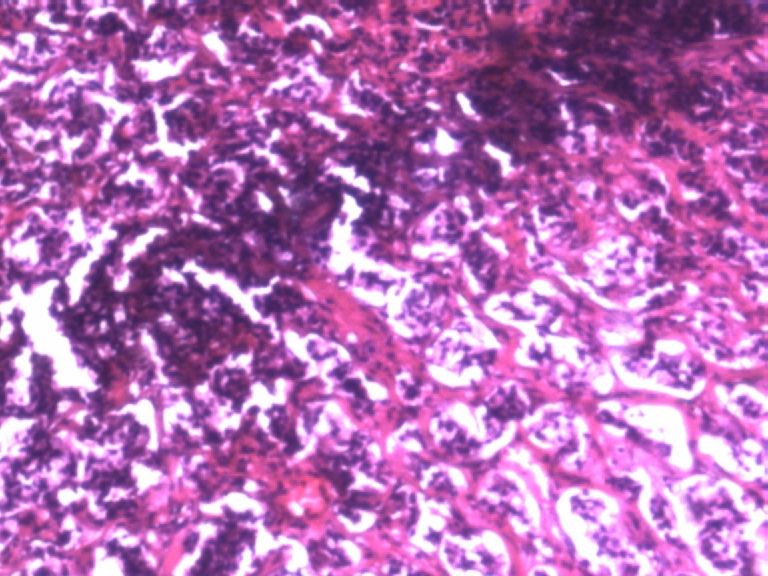

男,50岁,阑尾长7厘米,直径0.4---0.6厘米。剖开:尖端看见淡黄色区,不规则,界限欠清,0.15*0.2厘米,质中。

×参考诊断

考虑阑尾类癌

像类癌,有些粘液,标记一下Syn、CgA,有可能是杯状细胞类癌

按照胃肠胰腺神经内分泌肿瘤WHO2010分类,该例应属于NET G1(神经内分泌瘤,1级)。需标记Syn, CgA, Ki67.

倾向神经内分泌肿瘤,建议做CgA、SYN、Ki-67检查。

阑尾的神经内分泌肿瘤我们已经碰到好几例了,一般都在阑尾尖端,取材一定要规范,这样可以减少漏诊率。